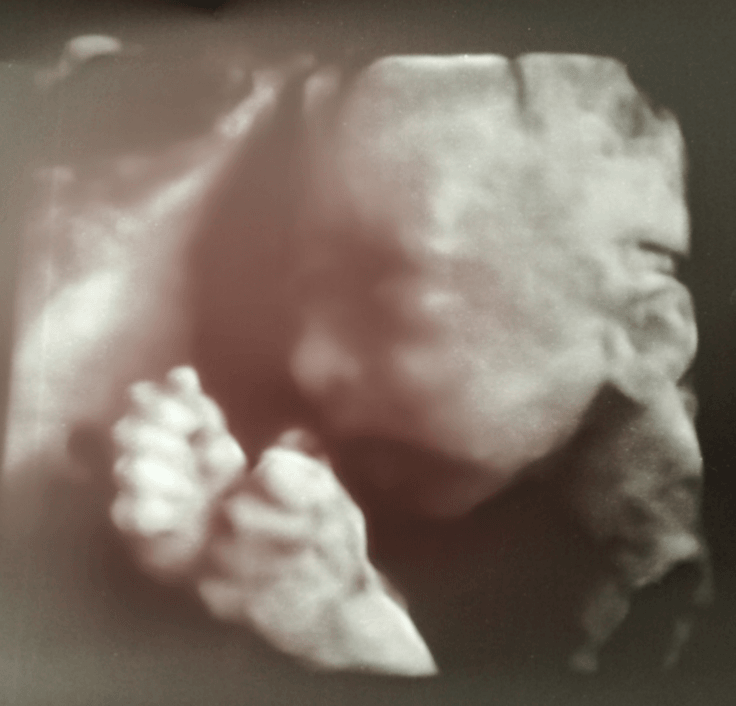

Najpiękniejsze kciuki ever!!Cześć Ciotki

Zobacz załącznik 854400

Który to tydzień?? I to jest USG 3d czy 4d ?Cześć Ciotki